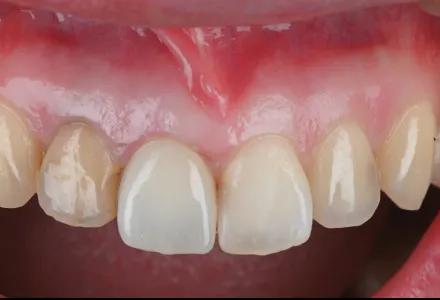

セラミック症例2

Before

After

- 治療名

- インプラント治療+セラミックの詰め物

- 患者さん

- 60代 男性

- 執刀医

- 田中院長

- 治療

内容 - 今回は奥歯を失われた患者様に対し、インプラント治療とセラミックの詰め物を行いました。セラミックを被せることで、噛む機能だけでなく審美面にも配慮した治療を行いました。患者様から「従来の銀歯のように目立つことがなく、白く自然な仕上がりにとても満足しています。機能面も見た目も両方改善され、田中院長に心から感謝しています。」とありがたいお言葉をいただきました。

- 治療期間

- 5ヶ月

- 治療費

- 1,000,000円~

- リスク

- 強い衝撃や歯ぎしりなどにより、欠けたり割れたりすることがあります。